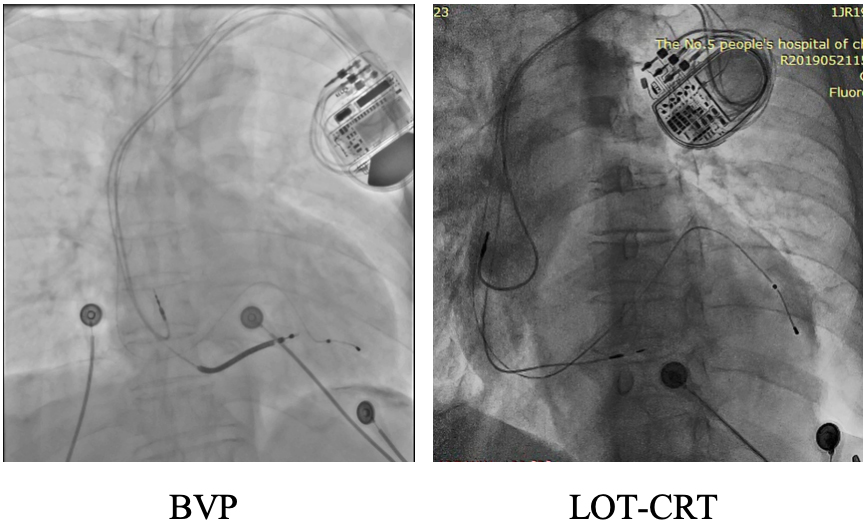

applied for six to eight hours using a sandbag (Fig. 1). All patients underwent

Fig. 1.

Representative chest X-rays from the first postoperative day are shown for both groups.